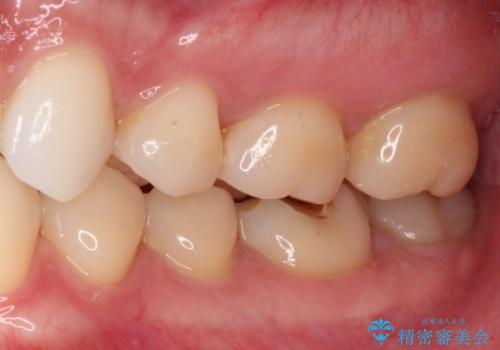

冷たいものがしみる症状はなくなり、舌で触ったときのザラザラ感もなくなりました。